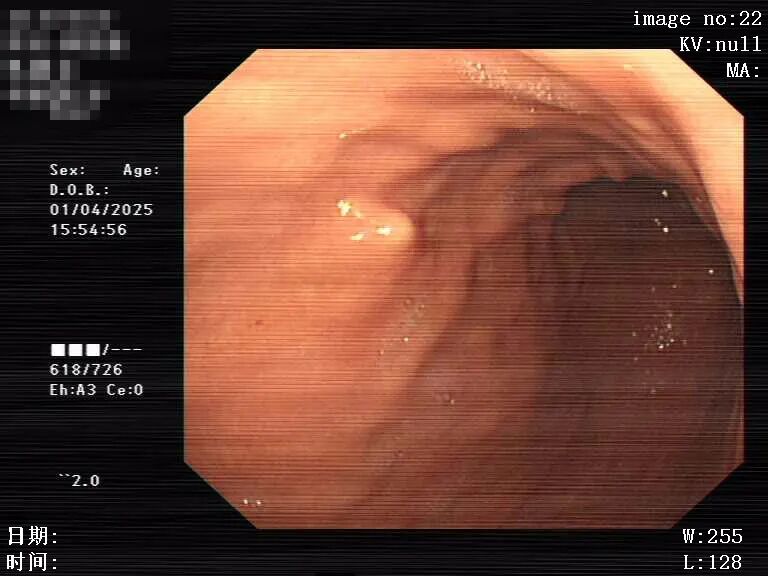

图片 图片

球囊扩张治疗中        体外定位确定穿刺点

经过消化内科团队综合评估患者病情以及多角度考虑治疗方案后,认为经内镜食管狭窄球囊扩张术联合经皮内镜下胃造瘘术(PEG)是最适合该患者的治疗方案。经过与患者家属充分沟通,患者同意采取这一治疗方案。消化内科团队凭借扎实的技术和丰富的经验,顺利为患者完成经内镜食管狭窄球囊扩张术后直接行经皮内镜下胃造瘘术(PEG)。术后,患者恢复良好,顺利出院。